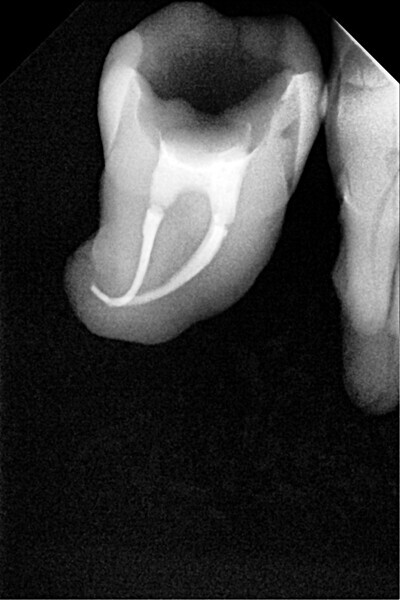

1. direct restoration using a fibre-reinforced flowable composite and membrane cube after endodontic treatment (Figs. 21–35); and

The second step focuses on reinforcing the restoration through careful fibre and FRC selection and placement. Tooth preparation should involve minimal removal of tooth structure to preserve as much natural tooth as possible in preparing the cavity for the restoration. Fibres or layers of FRC (flowable, paste, cube, etc.) are then strategically placed within the prepared tooth and composite material to reinforce areas susceptible to high stress and occlusal forces based on occlusal contact mapping. This strategic selection and placement of fibres and layers of FRC is crucial for enhancing the strength and longevity of the restoration.

Restore

The third step is to restore the tooth to its natural form, function and aesthetics. Composite resin, along with fibres or fibre-reinforced flowable or fibre-reinforced dentine substitute materials, is carefully applied to the prepared tooth structure. A layering technique is often used to ensure proper adhesion and integration of the reinforced materials with the composite material, enhancing the overall strength and functionality of the restoration. The composite resin is then polymerised using a curing light, ensuring that the materials are securely bonded within the restoration and providing a stable and long-lasting result. During this restorative process, the clinician should take special care not to expose fibres or FRC layers to the oral environment, as this can cause tissue irritation and water absorption by the materials in the long run. Therefore, the final layers of the restoration should always be a suitable aesthetic conventional composite resin.